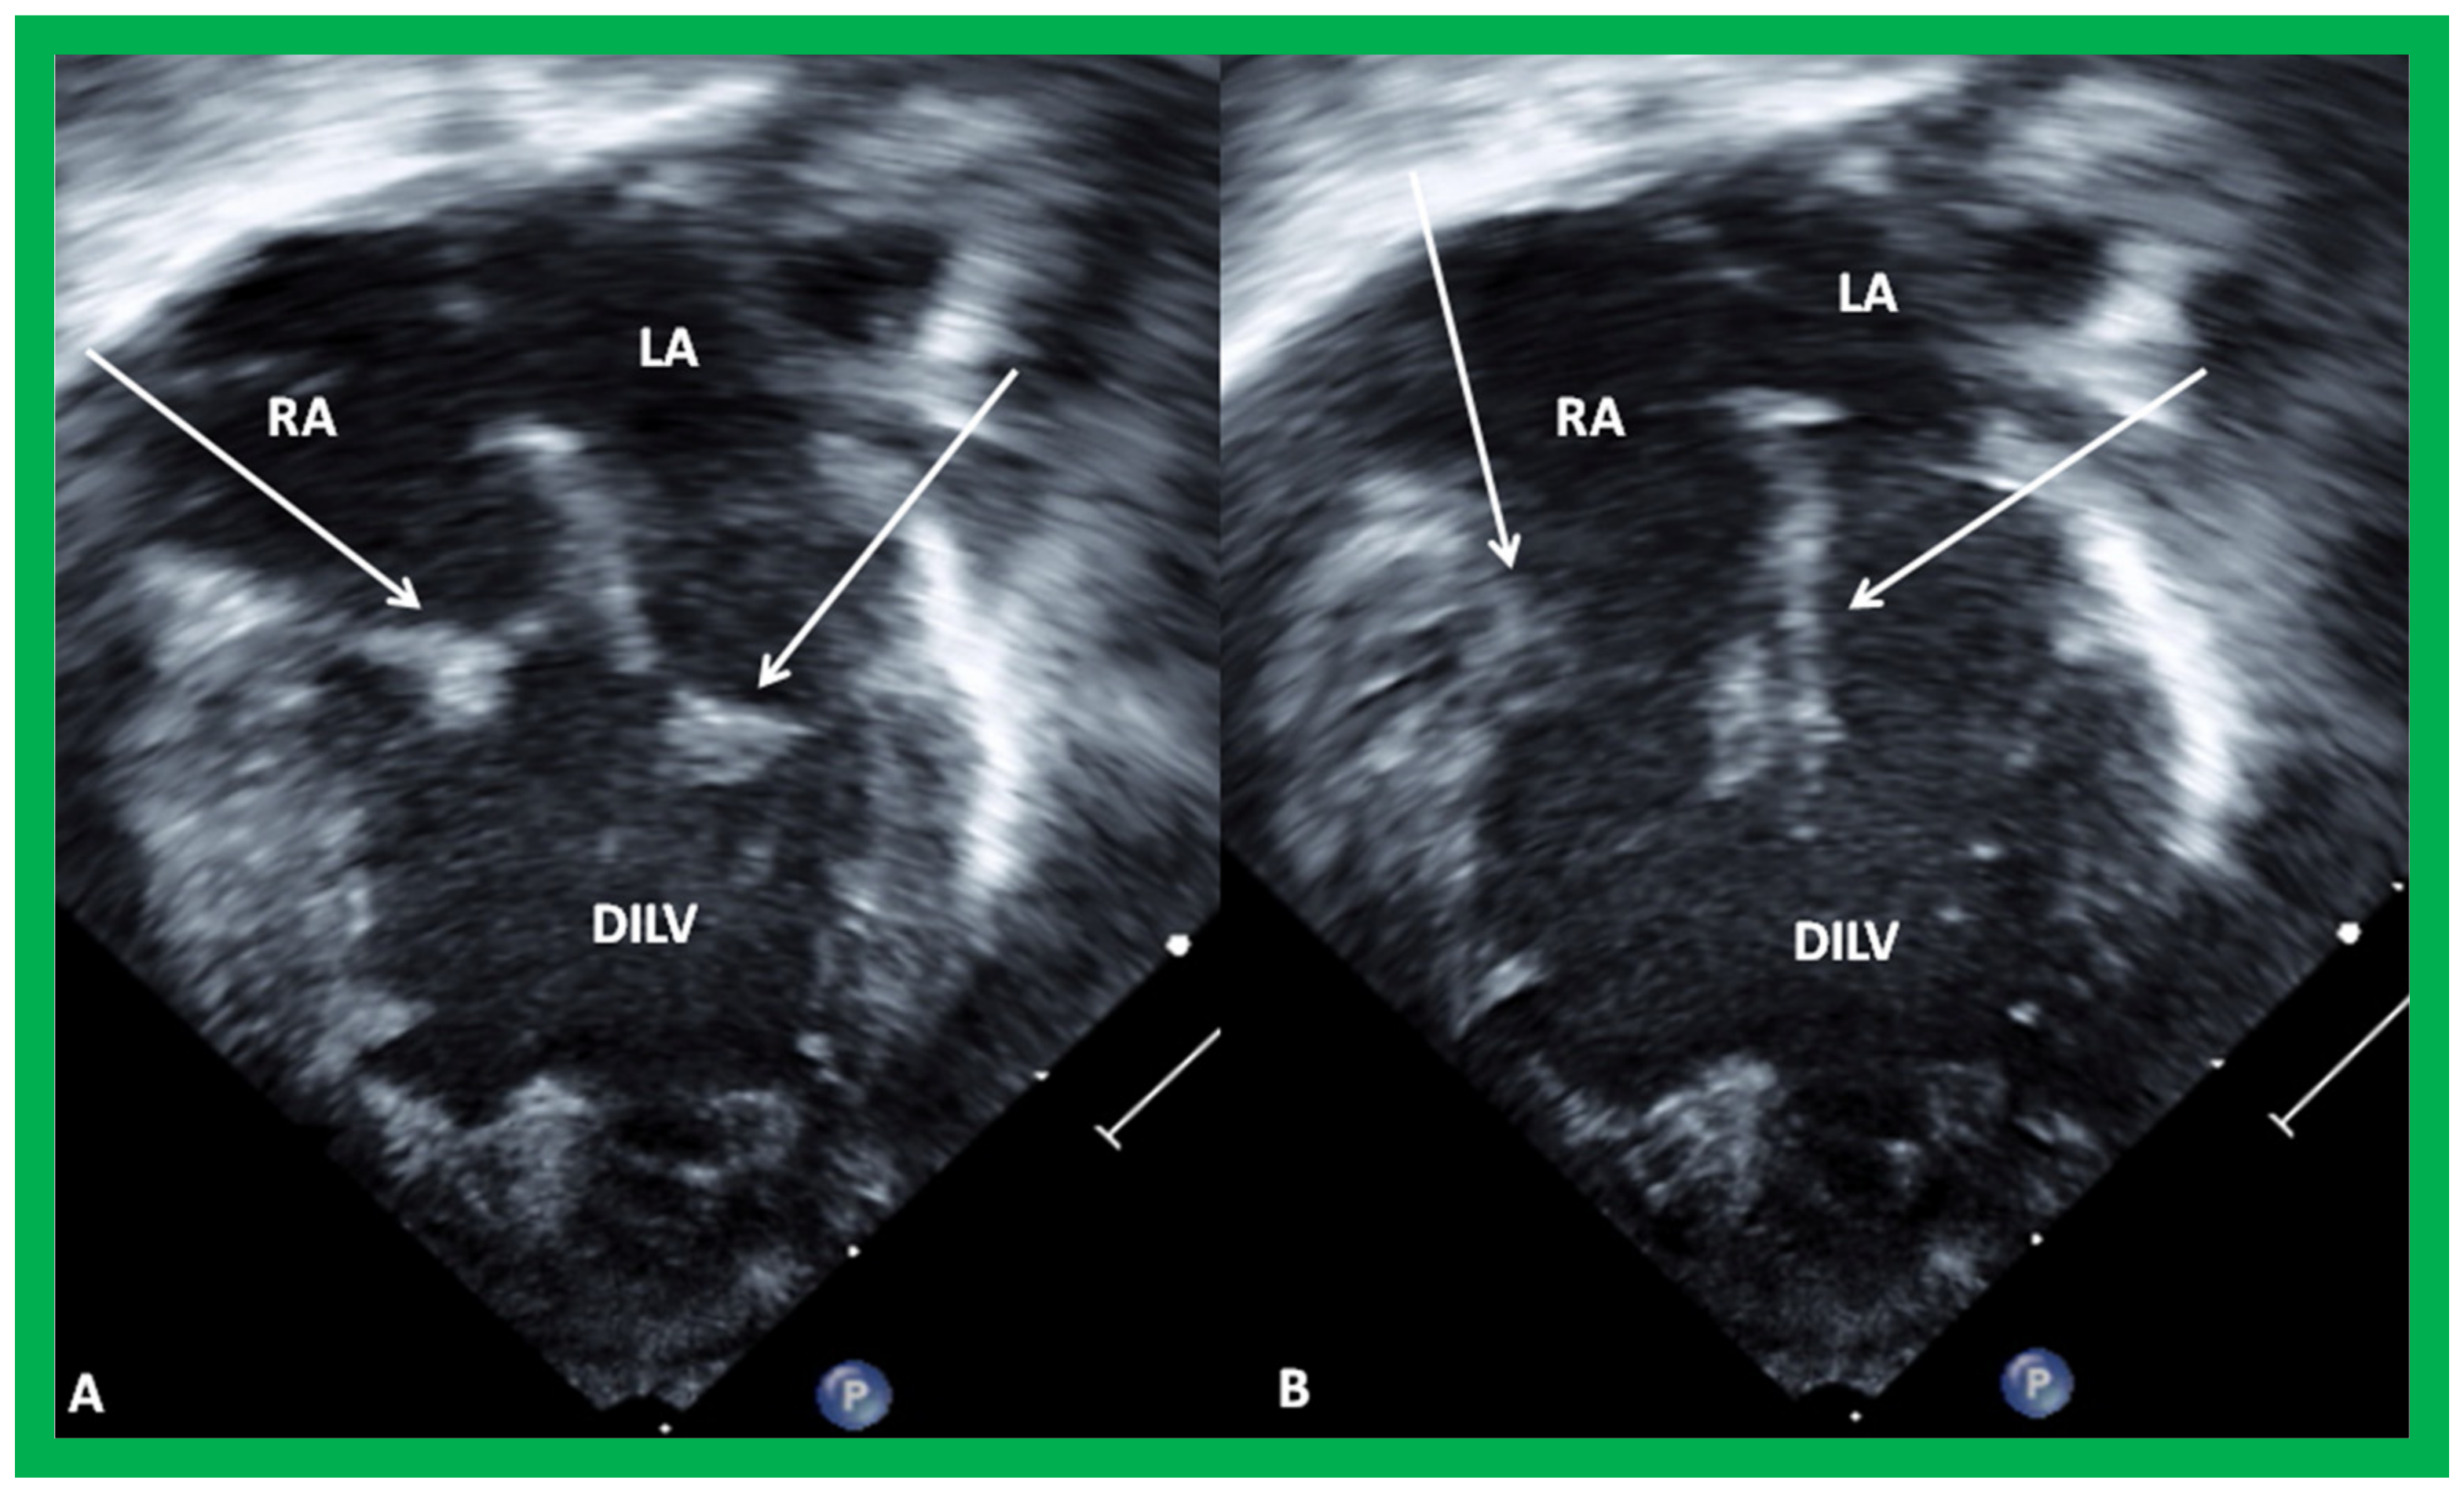

7. Echocardiogram